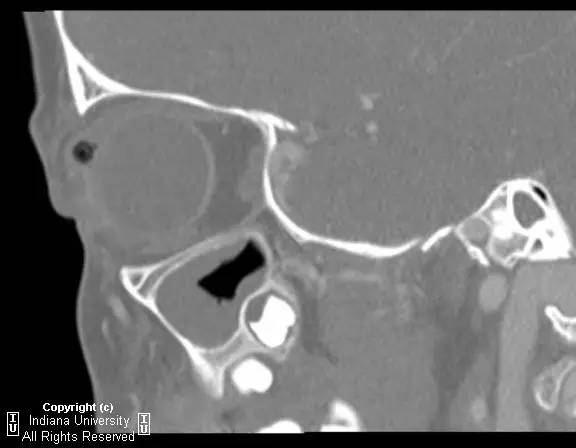

右侧上眼睑软组织肿胀。上眼睑与眼球间可见矩形积气,约1 cmx 0.4 cm x 0.4 cm,并线样影在内穿行。眼球及晶状体正常。眶隔后及眶内软组织无肿胀、血肿或脂肪条纹提示为创伤性。无对比剂外渗。无对急性骨异常。右侧上颌窦粘膜增厚。

【诊断】右上眼睑和眼球间木片存留

There is a piece ofwood between the superior right eyelid and the globe.